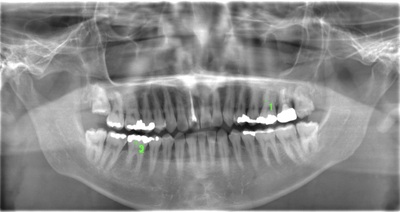

CASE 11

| 年齢・性別 | 33歳・男性 |

| 主訴 | 左上下親知らず抜きたい |

| 抜歯期間 | 30分 |

| 抜歯費用 | 約2,500円(保険内) 別途CT撮影で3,000円 (2022年7月現在) |

| 抜歯内容 | 左上下の親知らず抜歯 |

| 治療方針 |

初めに右下の奥歯が痛いとのことでご来院されました。 右下の親知らずと7番目の歯がカリエスになっていたため、まずは右下の親知らず抜歯と7番目の感染根管治療を行いました。左上下の親知らずもカリエスになっているため、今回抜歯を行いました。 |